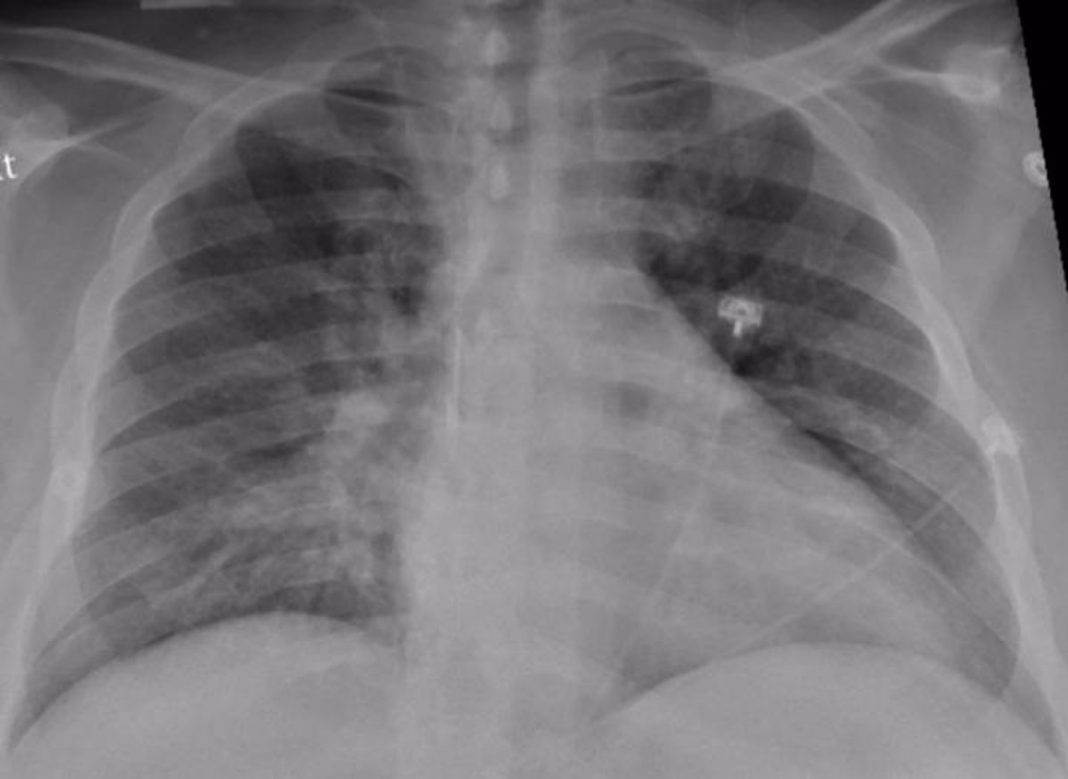

Sin lugar a dudas, el Covid es una afección que afecta primeramente a los pulmones, pero sus daños no se limitan a ese órgano porque también muchos otros tales como: corazón, riñones y cerebro, lo que sin lugar a dudas de ser persistentes en el tiempo, puede causar daños mayores a los mismos y complicaciones.

Esta persistencia del Covid, pueden incluir secuelas en los órganos mencionados, manifestándose problemas tales como: problemas respiratorios por mucho tiempo, problemas cardíacos, afecciones renales crónicas, accidente cerebrovascular, síndrome de Guillain-Barré (parálisis temporal) e incluso síndrome inflamatorio multisistémico donde los órganos y tejidos se inflaman de manera grave